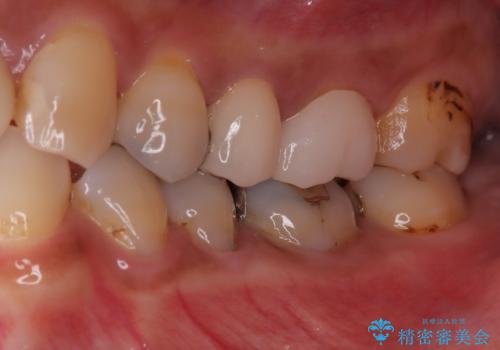

- 「何もしなくても歯が痛む、咬むと歯が痛む」を主訴に来院された患者さんです。検査の結果、歯髄の部分壊死と診断しました。根管治療を行いファイバーコアとオールセラミッククラウンで治療を行いました。

- 297,000円【根管治療110,000円+ファイバーコア22,000円+仮歯11,000円+オールセラミッククラウンスペシャル154,000円】費用は治療当時の料金となります

術前に神経の部分壊死と診断しましたが、神経をあけたときに出血が一切無かったので神経が死んでいるという診断は正しかったという事になります。

神経の処置にはマイクロスコープを使用しながら唾液を根管内に入れないようにラバーダムシートを使用しながら治療を行っています。